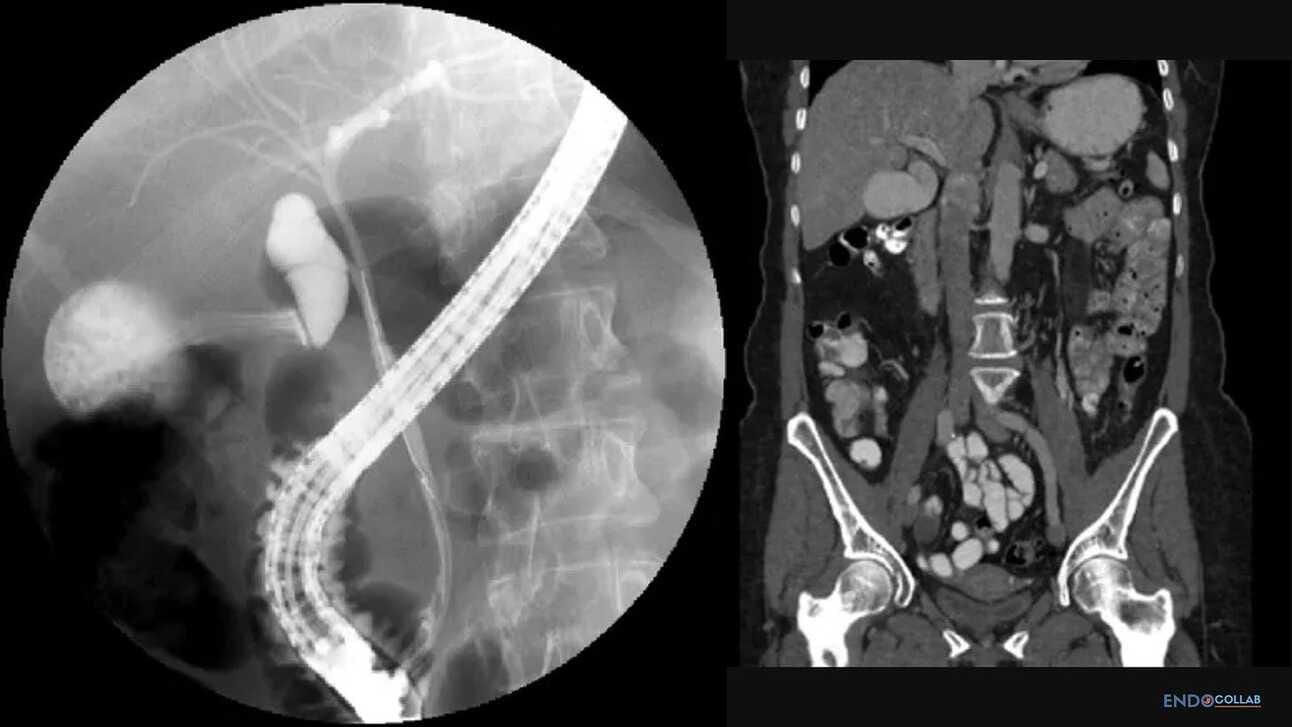

What is a Phrygian (Cap) Gallbladder?

A phrygian cap gallbladder is a congenital anomaly of the gallbladder with an incidence of 4%. It can simulate a mass in the liver during hepatobiliary imaging and is sometimes mistaken for pathology. A Phrygian cap, however, has no pathological significance and normally causes no symptoms.

The gallbladder is a pear-shaped organ measuring about 7 cm long and 3 cm wide and is located on the undersurface of the liver. Variations of the gallbladder include anomalies of form, location or number of gallbladders. A phrygian cap is the most common congenital abnormality of the gallbladder with an incidence of 4%. Although it can simulate a mass in the liver on radiological imaging studies, it does not have any pathological significance, and there is no need for cholecystectomy, unless it causes symptoms such as biliary colic or cholecystitis (1).